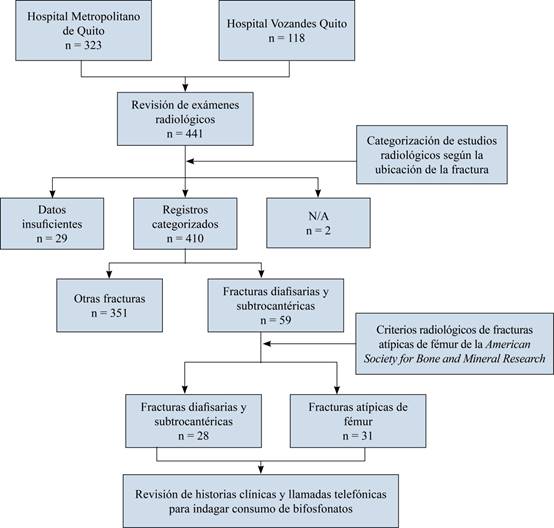

Se obtuvo un total de 323 registros del Hospital Metropolitano de Quito y 118 del Hospital Vozandes de Quito. Posteriormente se revisaron los exámenes radiológicos de los registros para clasificarlos en una de las siguientes categorías, según su ubicación: intertrocantérica, cuello de fémur, datos insuficientes, diáfisis de fémur, periprotésica, fémur distal, subtrocantérica, pseudoartrosis, fractura múltiple del fémur y cabeza femoral. Dos casos fueron clasificados como «no aplica» (N/A), ya que se trataban de un paciente que ingresó para retiro de material de osteosíntesis y otro con consolidación viciosa de fémur.

Una vez realizada dicha clasificación, se analizaron únicamente las fracturas de fémur subtrocantéricas (FS) y diafisarias (FD); y se aplicaron los criterios de la American Society for Bone and Mineral Research para la definición de caso de «fractura atípica de fémur» (FAF) en cada uno de los registros, por tres investigadores diferentes, realizando consenso en aquellos casos que existía diferencia de criterio. De tal forma se conformaron dos grupos: «fracturas atípicas de fémur» (FAF) y «fracturas diafisarias/subtrocantéricas de fémur» (FD/FS) (Figura 2).

Se analizó un total de 441 registros clínicos, de los cuales 98 (22.2%) eran del sexo masculino y 343 (77.7%) del femenino. Posterior a la revisión de los estudios radiológicos y clasificación de la ubicación de las fracturas en el fémur, se constató un total de 51 FS/FD. Tras la aplicación de los criterios de definición de FAF, se determinó la existencia de 31 casos (Figura 3).